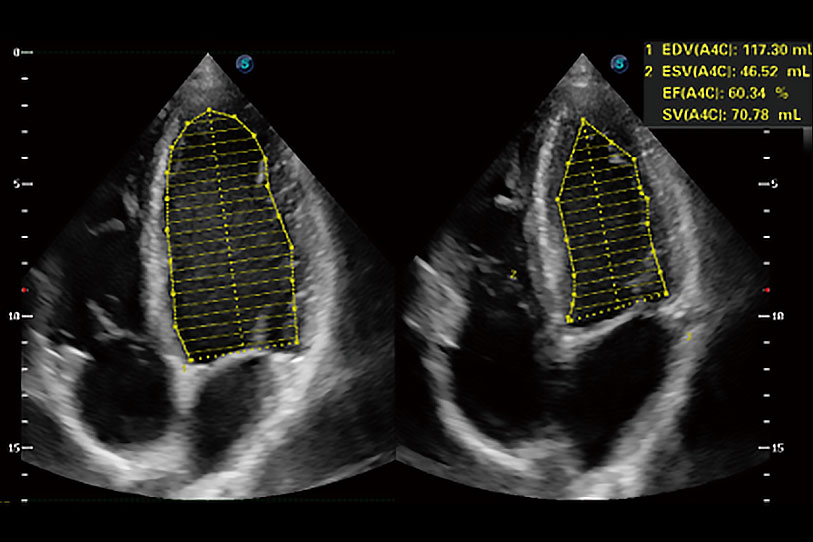

能夠基于左心室壁追蹤和辛普森法,自動(dòng)計(jì)算射血分?jǐn)?shù),支持多個(gè)可移動(dòng)點(diǎn)描跡,與手動(dòng)測(cè)量相比,極大節(jié)省了動(dòng)物醫(yī)生的時(shí)間和精力。